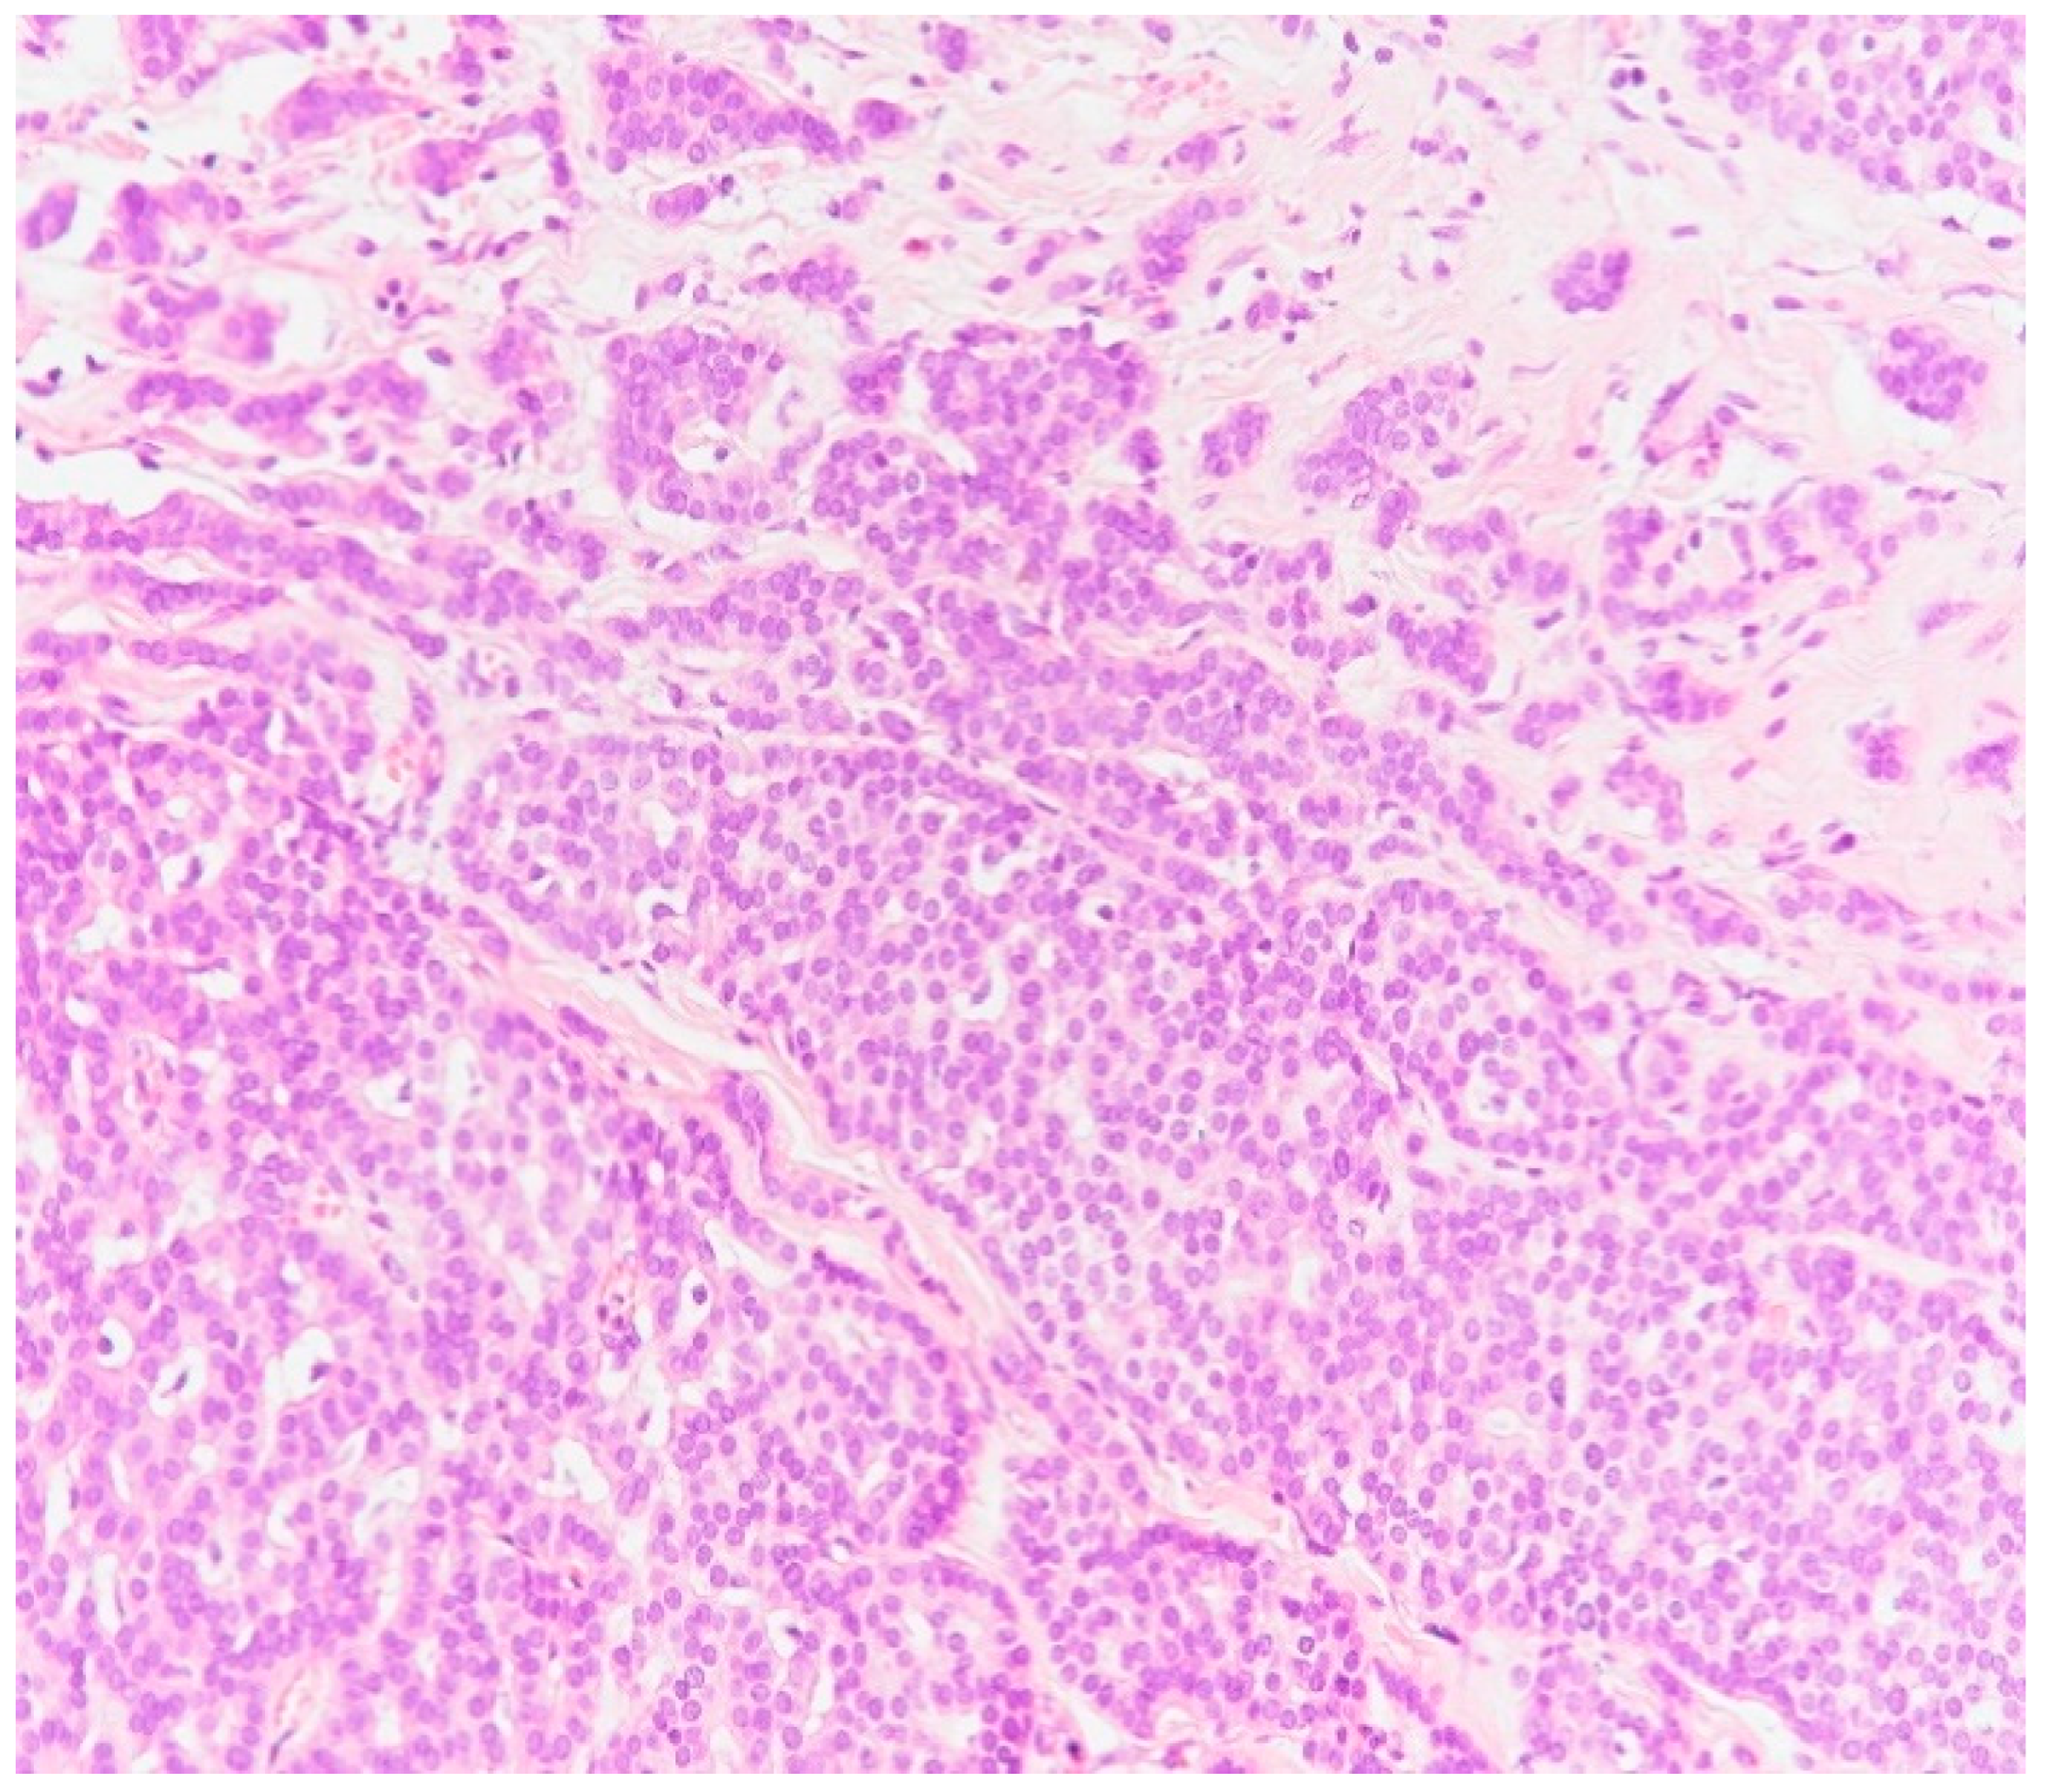

2. Case Presentation

3. Discussion